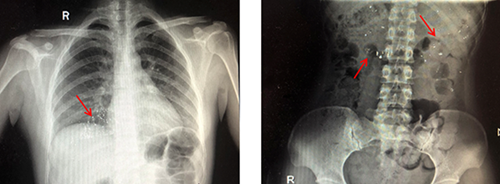

醫(yī)生解釋,水銀體溫計是由玻璃和金屬汞構(gòu)成,咬碎后的碎片可能會導(dǎo)致口腔、咽喉部、胃腸道黏膜的損傷,嚴(yán)重者甚至?xí)?dǎo)致穿孔。水銀經(jīng)胃腸道吸收甚微,但誤吞水銀者如果胃腸道黏膜有潰瘍傷口,水銀便會經(jīng)潰瘍或者傷口立刻進入人體血液,這樣吸收的汞會產(chǎn)生較大的毒性,嚴(yán)重可危及生命安全。而及時攝入蛋清、牛奶等可有效保護消化道黏膜,減少毒物的吸收。后經(jīng)急診科醫(yī)護人員進行專業(yè)的清理口腔,洗胃,催吐,加速排泄等措施,終于將孩子腸胃內(nèi)殘留的水銀排泄干凈。